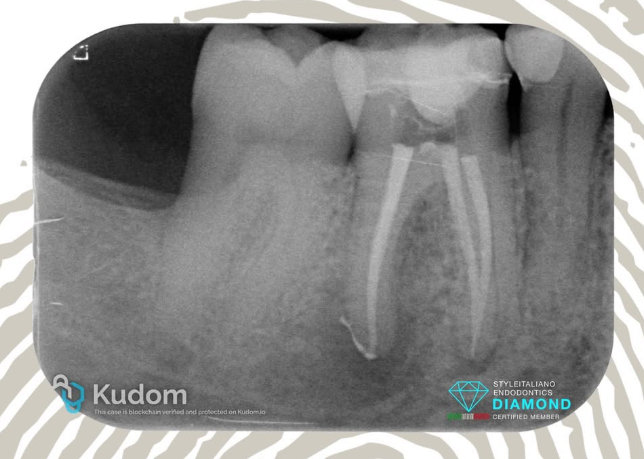

4.6: SINGLE VISIT RETREATMENT - L.E.O - 7 YEARS RECALL

A large periapical lesion was present on the mesial root of tooth 4.6, which had been previously treated many years ago and restored with a fiber post and crown.

The patient requested that the retreatment be performed through the crown, despite being informed that this was not the ideal approach.

After removal of the fiber post using an ultrasonic tip, the tooth was desobturated with rotary files, then shaped, thoroughly cleaned, and obturated in the same session.

CeraSeal bioceramic sealer was used with the Cold Hydraulic Condensation (CHC) technique, as the tooth was asymptomatic and no exudate was present in the canal.

The 1-year recall showed the not yet completed healing of the lesion and a fracture of the crown.

At the 7-year recall, complete healing of the large lesion was observed — it’s all about the outcome.

ARE BIOCERAMIC SEALER AND CHC RELIABLE? IT’S ALL ABOUT OUTCOME, NO FOLLOW UP NO ENDO.